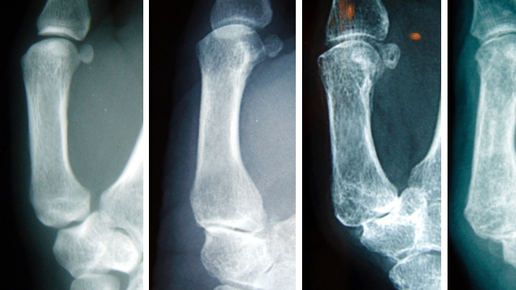

Заболевания, при которых происходит постепенное изменение структуры и разрушение (дегенеративно-дистрофические изменения) суставных тканей, называются артрозами. Патология может затрагивать любой сустав в теле человека, в том числе и мелкие сочленения кистей. При поражении сустава у основания большого пальца – запястно-пястного сочленения – говорят о ризартрозе. Ризартроз – довольно распространенная патология, которая составляет порядка 5% всех заболеваний кисти. Он даже представлен в Международной...

Ризартроз или артроз первого запястно-пястного сустава является распространенным заболеванием, поражающим преимущественно женщин старше 50 лет. Он возникает, когда хрящ в суставе большого пальца изнашивается, что приводит к боли, отеку и тугоподвижности.   Ортезы для большого пальца обычно используются в качестве консервативного лечения артрита большого пальца.Они могут помочь облегчить боль и уменьшить воспаление, обеспечивая поддержку и неподвижность сустава.   В одном исследовании, опубликованном...